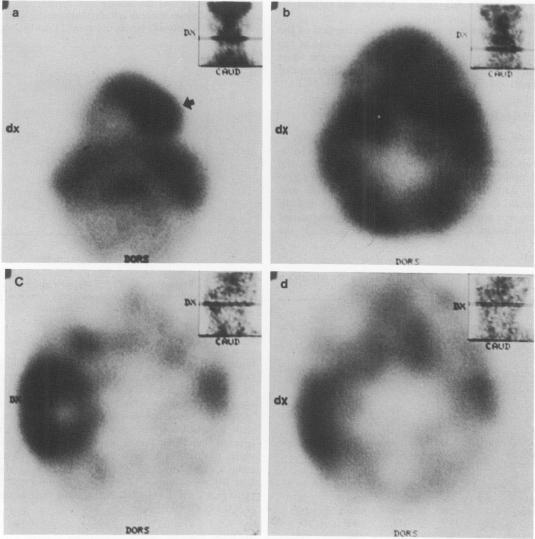

Twenty patients with malignant head and neck tumours were imaged with 99Tcm-labelled hexamethylpropylene amine oxime (HMPAO), a radiopharmaceutical generally used for blood flow studies. Before radiotherapy (RT), 93% of the tumours could be detected with single photon emission computed tomography (SPECT) and 45% with planar imaging. Whole tumour-to-background 99TcmHMPAO uptake ratios ranged from 3.6 to 1.0 (mean 1.7 +/- 0.6) in untreated tumours. There was a good correlation between tumour volume and uptake (r = 0.69, P = 0.002). Sixteen patients were reimaged during or shortly after radical RT. 99TcmHMPAO uptake was significantly lower after treatment (mean uptake ratio 1.2 +/- 0.3, P less than 0.001). However, RT associated changes in 99TcmHMPAO uptake were in agreement with the clinical response in only 63% of the studies. This study indicates that 99TcmHMPAO SPECT imaging can be used for pretherapeutic localisation of head and neck tumours. Although most tumours show a decrease in uptake after irradiation the poor association with tumour regression does not allow for reliable assessment of treatment response.

20例头颈部恶性肿瘤患者用99锝标记的六甲基丙烯胺肟(HMPAO)进行成像,HMPAO是一种常用于血流研究的放射性药物。放疗(RT)前,单光子发射计算机断层扫描(SPECT)可检测出93%的肿瘤,平面成像可检测出45%的肿瘤。未经治疗的肿瘤中,肿瘤与背景的99锝-HMPAO摄取率范围为3.6至1.0(平均1.7±0.6)。肿瘤体积与摄取之间存在良好的相关性(r = 0.69,P = 0.002)。16例患者在根治性放疗期间或放疗后不久再次成像。治疗后99锝-HMPAO摄取显著降低(平均摄取率1.2±0.3,P<0.001)。然而,在仅63%的研究中,99锝-HMPAO摄取的放疗相关变化与临床反应一致。本研究表明,99锝-HMPAO SPECT成像可用于头颈部肿瘤的治疗前定位。尽管大多数肿瘤在照射后摄取减少,但与肿瘤消退的相关性较差,无法可靠评估治疗反应。